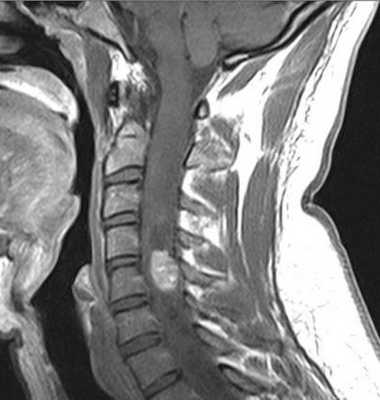

Атрофией считается уменьшение передне-заднего измерения спинного мозга по результатам МРТ меньше 7 мм в шейном отделе и меньше 6 мм в грудном. Участок атрофии при МРТ может быть локальным или протяжённым, если он распространяется более чем на 2 позвонковых сегмента. Граница атрофии на Т2-взвешенных МРТ нечёткая. Распространённая атрофия является типичным отдалённым последствием спинальной травмы.

МРТ шейного отдела позвоночника. Компрессия и атрофия спинного мозга. Т2-взвешенная сагиттальная МРТ.

Под разрывом спинного мозга понимают отсутствие его изображение при МРТ на протяжении участка на уровне травма или ниже его. Разрывы чаще наблюдаются в грудном отделе с частотой около 4%. Полный перерыв нередко сочетается при МРТ позвоночника с миеломаляцией и атрофией окружающего спинного мозга.

Спинной мозг может прикрепляться прочно к к стенке позвоночного канала, что даже приводит к его продольным разрывам. Часто при МРТ наблюдается весь комплекс изменений спинного мозга : диффузная атрофия, кисты и расщепление.